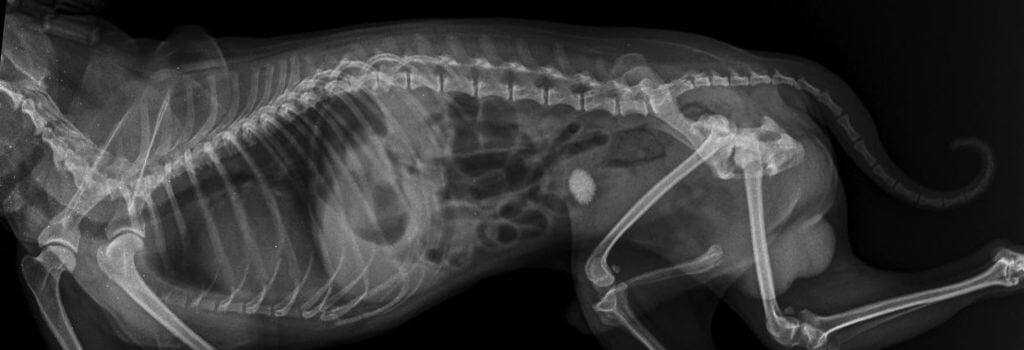

Radiography (X-ray imaging) is the most common diagnostic imaging procedure used in veterinary practices. It produces black, white, and gray images (radiographs) of bones, foreign objects, and large body cavities. Radiography is particularly useful for detecting fractures, tumors, injuries, infections, and deformities. In some cases, specialized X-ray techniques called contrast procedures are used to provide more detailed images of body organs.